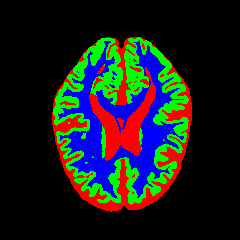

• MRBrainS13 [35]: From the MICCAI 2013 challenge, this dataset contains multi-sequence scans of 20 subjects acquired on a 3.0T Philips Achieva scanner. It provides T1 (TR: 7.97.9 ms, TE: 4.54.5 ms), T1-IR, and T2-FLAIR sequences. All scans are co-registered and bias-corrected with a voxel spacing of 0.96×0.96×3.000.96\times 0.96\times 3.00 mm. We utilize the provided labels for CSF, GM, and WM segmentation.

7 Qualitative Evaluation

Fig. 8 and Fig. 10 provide qualitative comparisons on the OASIS-1 and MRBrainS13 datasets, respectively. It is visually evident that the baseline predictions (c) and standard augmentations (e.g., (d), (g), (i)) frequently suffer from noisy artifacts, blurred boundaries, and mis-segmentation of intricate anatomical structures. In stark contrast, our ”Ours+” enhanced methods (e.g., (e), (h), (k)) consistently produce segmentation maps that are visibly cleaner, more spatially coherent, and demonstrate significantly sharper adherence to the Ground Truth (b). This superior fidelity is particularly noticeable in the complex sulcal patterns and holds true across all three backbones (rows), confirming that our framework yields more robust and anatomically plausible results.